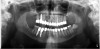

Figure 2  Vertical components of crown height space for a cement-retained restoration.

Figure 2